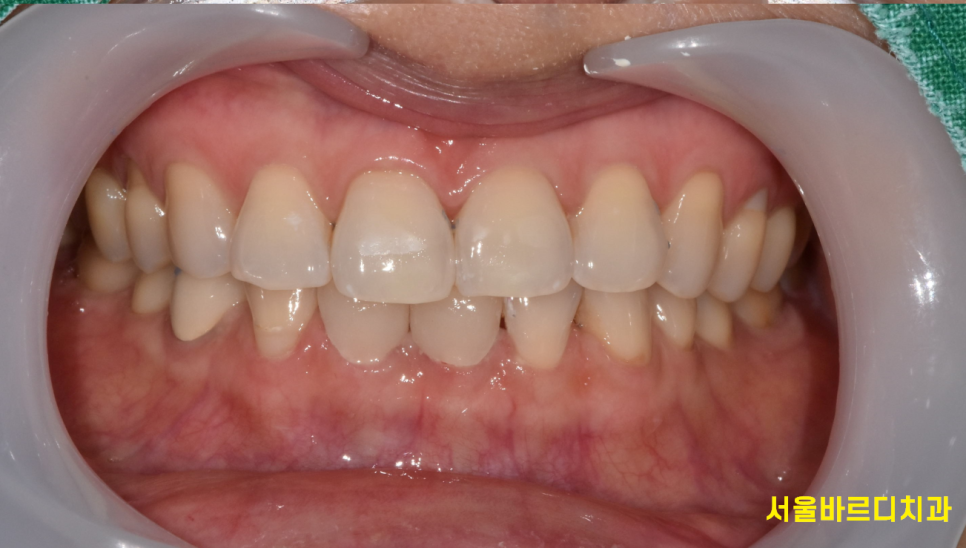

230608

앞니 벌어진 부분 틈새를 라미네이트를 통하여

메꿔드렸습니다.

치아 색상도 훨씬 밝아졌죠~?

이제 환하게 웃으세요 환자분~